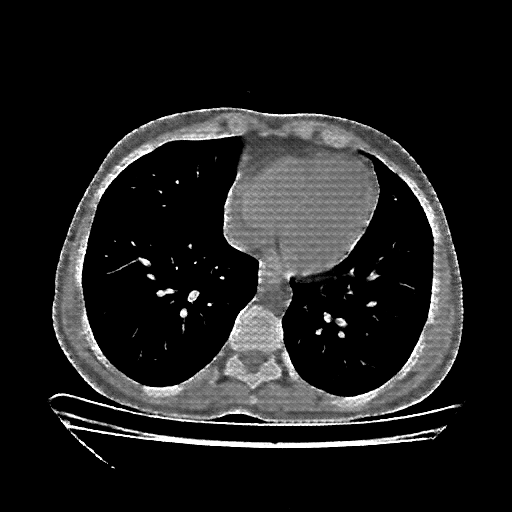

Reconstructed NATIVE CT scan (cycle consistency)

Full window (WL 1023.5, WW 4095 β†’ Low βˆ’1024, High +3071)

Lung window (WL -600, WW 1500 β†’ Low βˆ’1350, High +150)

Mediastinum window (WL 40, WW 400 β†’ Low βˆ’160, High +240)